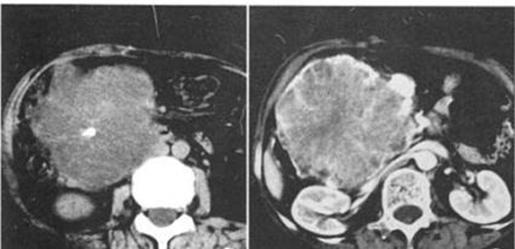

胰头肿瘤呈多个小囊聚集成“蜂窝”样,边缘光整,中央见小片状钙化

胰腺微囊型浆液性囊腺瘤的典型CT表现:胰腺实质内轮廓清楚的分叶状肿物,囊腔细小(<2cm)且多,呈”蜂窝样”改变,最具有特征性的是中央星状瘢痕、日光放射状钙化等,浆液性囊腺瘤生长缓慢,一般早期发现者可以采取定期观察的防范,等到较大时再考虑手术切除也来得及。